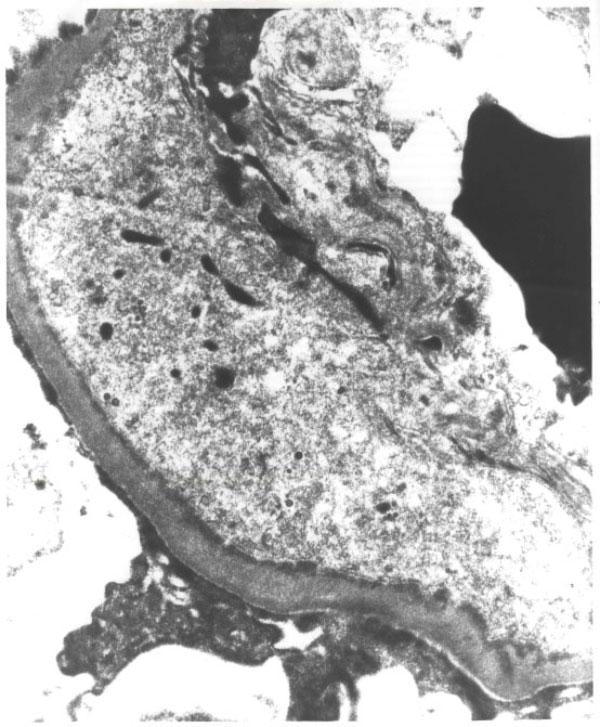

The current report describes a patient who presented with the abrupt onset of hypertension, mixed nephritic/nephrotic syndrome and acute renal failure. Kidney biopsy was consistent with membranoproliferative glomerulonephritis, type 1. Bone marrow biopsy performed in the evaluation of periaortic lymphadenopathy, hepatosplenomegaly, and thrombocytopenia confirmed the diagnosis of low grade B-cell non-Hodgkin's lymphoma. The patient's renal function improved and proteinuria resolved after initial treatment of non-Hodgkin's lymphoma with chemotherapy. During eleven years of follow up, membranoproliferative glomerulonephritis has remained in remission, as confirmed by repeatedly negative urinalyses, normal blood pressure and absence of clinical signs and symptoms suggestive of nephritic/nephrotic syndrome.

本报告描述了一名患者,其突然出现高血压、混合性肾炎/肾病综合征及急性肾衰竭。肾脏活检符合1型膜增生性肾小球肾炎。在评估腹主动脉旁淋巴结肿大、肝脾肿大及血小板减少症时进行的骨髓活检确诊为低度B细胞非霍奇金淋巴瘤。该患者在接受非霍奇金淋巴瘤化疗初始治疗后,肾功能改善,蛋白尿消失。在11年的随访中,膜增生性肾小球肾炎一直处于缓解状态,多次尿液分析阴性、血压正常以及无提示肾炎/肾病综合征的临床体征和症状均证实了这一点。